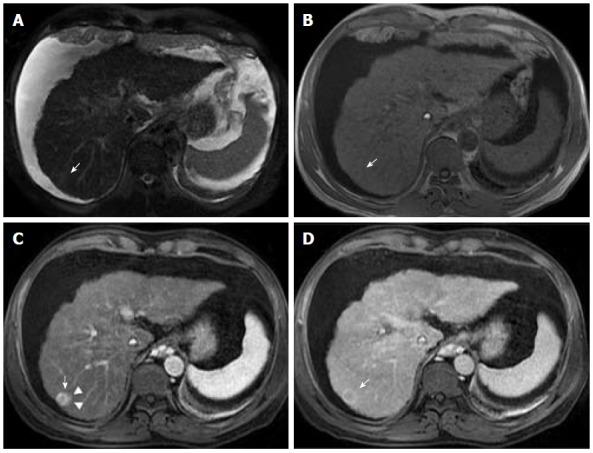

Hepatocellular carcinoma (HCC) usually develops in the setting of chronic liver disease. In the adequate clinical context, both multiphasic contrast-enhanced CT and magnetic resonance imaging are non-invasive modalities that allow accurate diagnosis and staging of HCC, although the latter demonstrates greater sensitivity and specificity. Imaging criteria for HCC diagnosis rely on hemodynamic features such as hyperenhancement in the arterial phase and washout in the portal or equilibrium phase. However, imaging performance drops considerably for small (< 20 mm) nodules because their tendency to exhibit atypical enhancement patterns. In order to improve accuracy in the diagnosis and staging of HCC, particularly in cases of atypical nodules, ancillary features, ., imaging characteristics that modify the likelihood of HCC, have been described and incorporated into clinical reports, especially in Liver Imaging Reporting and Data System. In this paper, ancillary imaging features will be reviewed and illustrated.

肝细胞癌(HCC)通常在慢性肝病背景下发生。在适当的临床背景下,多期对比增强CT和磁共振成像都是非侵入性检查方法,可实现HCC的准确诊断和分期,尽管后者具有更高的敏感性和特异性。HCC诊断的影像学标准依赖于血流动力学特征,如动脉期强化和门脉期或平衡期廓清。然而,对于小(<20mm)结节,其成像表现会显著下降,因为它们倾向于表现出非典型强化模式。为提高HCC诊断和分期的准确性,特别是非典型结节病例,已描述了辅助特征,即改变HCC可能性的影像学特征,并将其纳入临床报告,尤其是肝脏影像报告和数据系统。本文将对辅助影像学特征进行综述和说明。